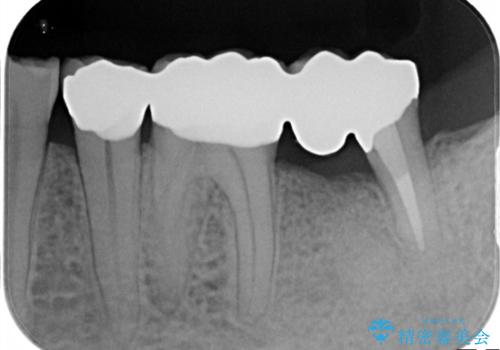

条件が少しでもよくなる様に、再生治療および確定外科を行い良好な歯周状態でオールセラミッククラウンを装着しております。

今回の症例は遠心根を保存するメリット・デメリットを患者さんと話し合い、治療を進めております。